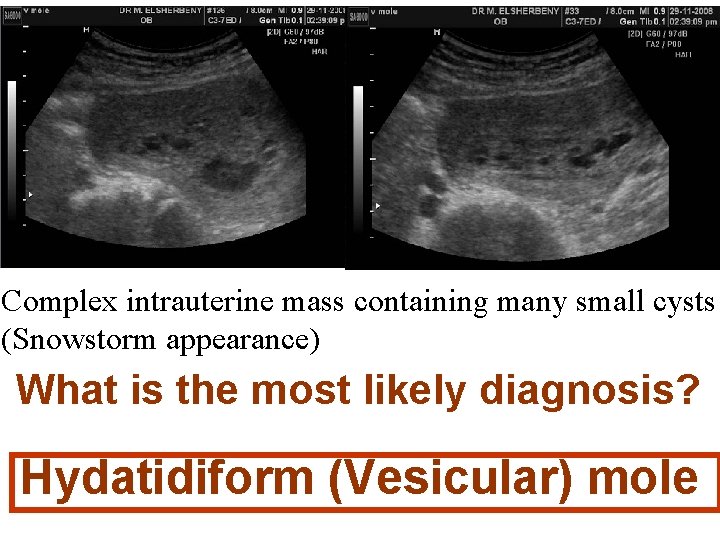

Complete hydatidiform mole. The classic "snowstorm" appearance is created by the multiple placental vesicles.

Complete H. Mole (High-resolution) U/S Complex intrauterine mass containing many small cysts. Complete H. Mole Associated theca-lutein cysts. U/S Power Doppler

Complex intrauterine mass containing many small cysts (Snowstorm appearance) What is the most likely diagnosis? Hydatidiform (Vesicular) mole

1 -What Is The Most Likely Diagnosis? The snowstorm pattern on U/S& The abnormally high h. CG level are diagnostic of Vesicular Mole Probably complete V. mole

Why It Is Probably Complete V. Mole? It demonstrates the typical U/S appearance of complete V. mole : a complex, echogenic intrauterine mass containing many small cystic spaces. Fetal tissues and amnionic sac are absent However the final differentiation is after histopathology.